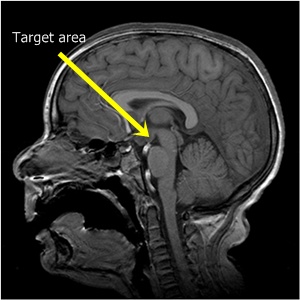

One of the first five patients treated with the MRI-guided laser procedure is Keagan Dysart. The nine-year-old from Converse, Texas, was diagnosed with a hypothalamic hamartoma. Though benign, this type of tumor is often intertwined with the hypothalamus, which regulates critical functions such as maintaining body temperature, blood pressure and electrolyte balance. The hypothalamus also sits very close to the brain stem and optic nerve.

The condition resulted in so-called gelastic seizures, causing regular uncontrollable giggling, as well as the more recognizable epileptic symptom of a tonic seizure, causing body stiffening. Because of the size and position of the hamartoma, Keagan’s case would have been particularly high-risk with a conventional craniotomy, with the potential to damage the vision system, pituitary gland, or cause diabetes insipidus, a potentially fatal condition that stops the ability of the kidneys to conserve water, and which is caused by damage to the part of the brain that releases an anti-diuretic hormone.